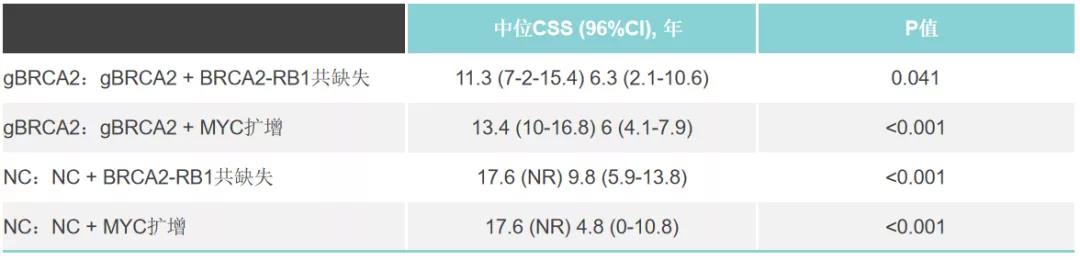

编者按前列腺癌存在“乌龟、兔子、老鹰”等三种不同进展速度的状态,携带BRCA2胚系突变的前列腺癌往往预后较差,是不折不扣的“鹰派”角色。如何深入挖掘此类患者的生物...